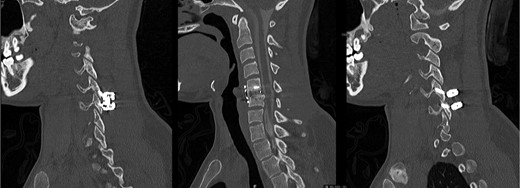

The patient’s Subaxial Cervical Spine Injury Classification (SLIC) score was 8, indicating a surgical lesion [5]. The patient was initially placed in cervical traction, with successful realignment at 30 lbs of weight. Surgical options were discussed at length with the patient, including an anterior only approach, followed by immobilization in cervical collar, versus a circumferential approach. The patient chose the latter, anticipating a more intense physical therapy for postoperative recovery. In the operating room, a singel level C5-6 anterior discectomy and fusion was initially performed, followed by a posterior approach with lateral mass screws and rods at C5 and C6. The disc was found to be severely disrupted, as expected, but no dural violation was observed. The patient had an excellent postoperative course, with immediate resolution of the hand pain and progressive return of motor function. She was transferred to the hospital’s inpatient rehabilitation center and at 2 weeks postoperatively she only exhibited trace weakness (4+/5) in the left leg and right triceps. At the 6month postoperative visit, the patient had no residual deficits and a CT-myelogram showed good incipient fusion across the disc space (Fig. 2).

Postoperative CT-myelogram, sagittal images through the left (left), center (center) and right (right) sides, illustrating good realignment and incipient fusion at C5-6.